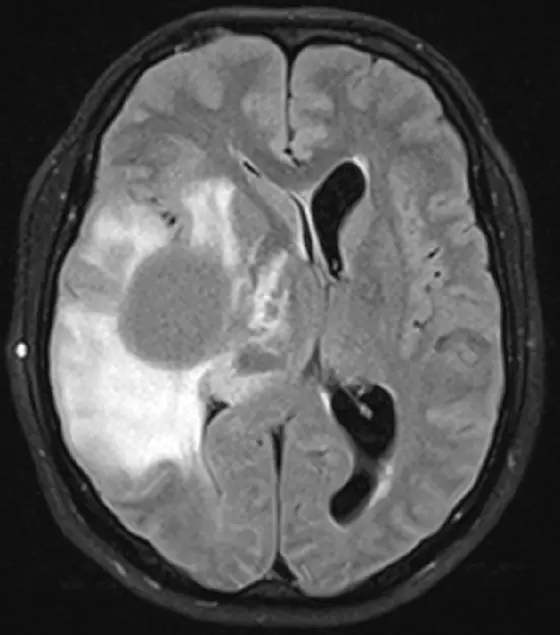

MRI image of diffuse glioma (top).

Diffuse gliomas are usually incurable brain tumors that spread in the brain and are difficult to remove completely by surgery. Chemotherapy and radiotherapy often only have a limited effect too. In many cases, diffuse gliomas share a common feature: in more than 70 percent of patients, the tumor cells have the same gene mutation. An identical error in the DNA causes a single, specific protein building block to be exchanged in the IDH1* enzyme. This creates a novel protein structure, known as a neo-epitope, which can be recognized as foreign by the patient's immune system.